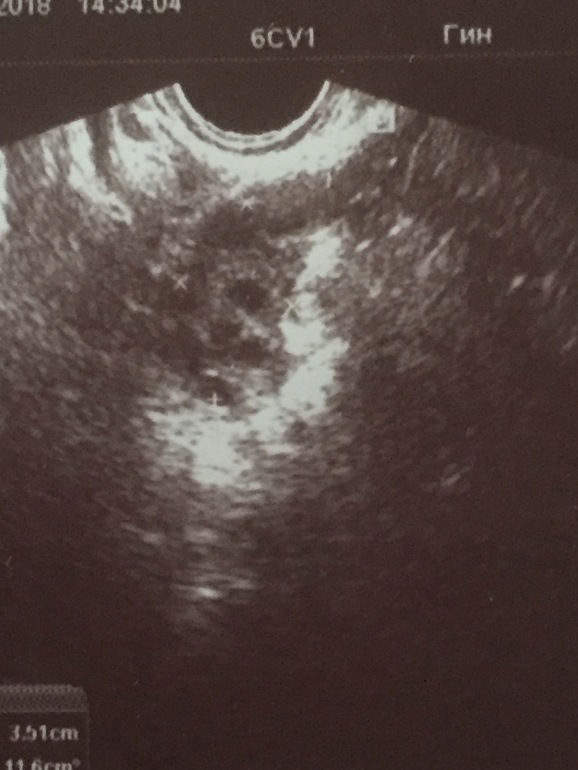

Была сегодня на УЗИ малого таза,врач говорит есть свободная жидкость в заднем своде в небольшом количестве.Спрашиваю значит прошла овуляция,говорит что да!

Потом говорит что она не видит доминантного фолликулах.

Говорит все чисто все хорошо,я спрашиваю ну Мои не овуляция что тогда раз болит и справа и слева иногда в ногу отдаёт.Говорит у вас поликистоз наверное...вообщем она сама не чего не знает,прикрепляю фото посмотрите